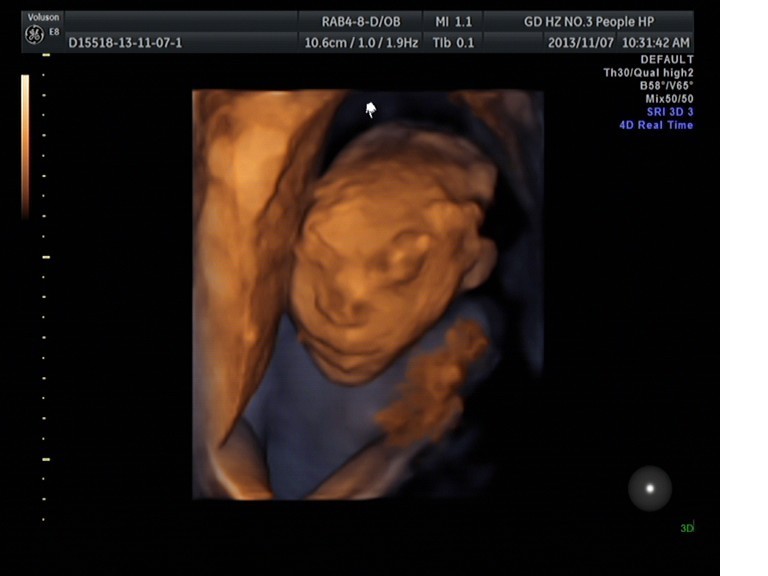

我院超声科筛查出多例脑膜脑膨出畸形胎

近期我院超声科在胎儿早中孕筛查时发现多例脑膜脑膨出的畸形胎儿。其中一例是目前我院发现最早的脑膜脑膨出畸形胎,孕约12周多。当时那个孕妇是过来做胎儿早期NT筛查的,超声科曾曦医生检查时发现胎儿颅骨光环回声中断,可见混合性肿块突出,并且NT值偏高,可疑脑膜脑膨出。于是曾曦医生立即邀请马晓芹主任过来会诊,结果证实了该胎儿的确有脑膜脑膨出畸形,建议终于妊娠。

脑膨出超声诊断要点是胎儿颅骨高回声环的延续性中断,局部向外突出囊性物,使头部变形。根据囊内容物回声特征可判断膨出物来源。若囊内为液性暗区则为脑膜膨出,内为实性的脑组织结构则为脑膜脑膨出。在鉴别诊断上,脑膜膨出容易与囊状淋巴管瘤相混淆,但囊状淋巴管瘤时,骨质无缺损,颅骨是完整的。超声医生应进行多方位、多切面的仔细扫查,方能为临床终止妊娠提供可靠的依据。

胎儿脑膜脑膨出是临床上胎儿发育中先天性畸形的一种,对其作出早期诊断非常重要。我院引进了目前全球最领先的以胎儿四维彩超为主的高分辨率全身彩色多普勒超声诊断仪Voluson E8,先进的设备加上优秀的人才,使得我院超声科的诊断水平越来越高,使得我们对胎儿畸形筛查的把关口已经从中孕期(孕约2025周)提前到早孕NT期(孕1114周)。这样不单单可以对部分先天性胎儿畸形可以作出早期诊断、及时终止妊娠,还可以大大减少对孕妇身体的伤害,更多的是减少这些家庭的经济压力与精神负担。